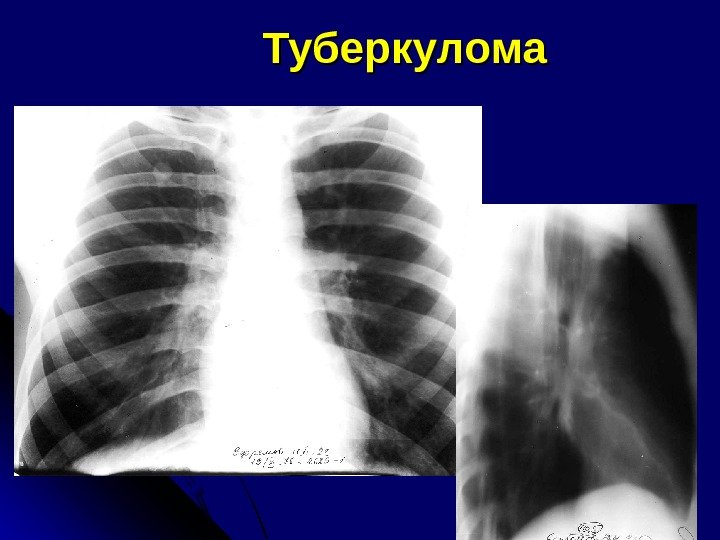

Туберкулома

Р-признаки Туберкулома Рак Локализация В передних сегментах в 2, 7% 47% S 3 Менее 1% 29% Величина 1 -3 см, 4 -5 см и больше Наружные контуры Лучистость, бугристость при небольших размерах Наличие дренирующего бронха Достоверный признак Может быть дорожка лимфангита Уменьшение размеров образования Зафиксированное на серии снимков Не бывает Увеличение размеров образования бывает Более характерно Наличие полости распада Эксцентрично располож. , щелевидная, неправильно округлая форма полости с гладкими четко очерченными стенками севестр или глыбки извести в полости, свежие туберк. изменения вокруг, деформация кон туров приводящего бронха Полость с горизонталь ным уровнем или без него, нечеткость и подрытость внутреннего контура полости, вхождение и обрыв бронхов в патолог. Образовании Наличие туберкулезного фона + — +